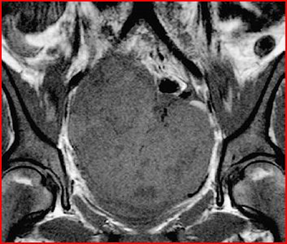

MRI shows a mass-free uterus, with no evidence of normal ovaries. The masses are approximately 13 cm in diameter and have low signal intensity on T1-weighted images and increased avidity after gadolin administration. On T2-weighted images the mass is hyperintense and the peripheral lesions probably correspond to ovarian follicles (Figures 4-6).

Figure 4: Axial T1-weighted MRI image, showing low signal intensity of the mass

Figure 5: Coronal T1-weighted MRI image, performed by administration of intravenous gadolin, shows low signal intensity of the mass, the black arrow highlights an increase in the septal area. The second mass, white arrow, extends into the upper left quadrant.

Figure 6: Sagittal T2-weighted MRI image of the pelvis, shows that the ovarian mass posterior to the uterus has an heterogeneous, intermediate-high signal intensity, the follicles in the periphery (arrow points), have a high signal intensity. The asterisk highlights the free liquid in the Douglas cord.